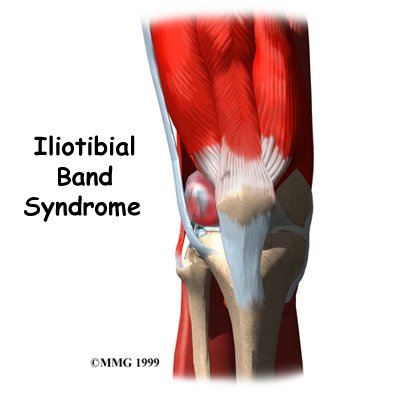

Iliotibial band (ITB) syndrome is an overuse problem that is often seen in bicyclists, runners, and long-distance walkers. It causes pain on the outside of the knee just above the joint. It rarely gets so bad that it requires surgery, but it can be very bothersome. The discomfort may keep athletes and other active people from participating in the activities they enjoy.

The ITB is actually a long tendon. (Tendons connect muscles to bone.) It attaches to a short muscle at the top of the pelvis called the tensor fascia lata. The ITB runs down the side of the thigh and connects to the outside edge of the tibia (shinbone) just below the middle of the knee joint. You can feel the tendon on the outside of your thigh when you tighten your leg muscles. The ITB crosses over the side of the knee joint, giving added stability to the knee.

The lower end of the ITB passes over the outer edge of the , the area where the lower part of the femur (thighbone) bulges out above the knee joint. When the knee is bent and straightened, the tendon glides across the edge of the femoral condyle.

A bursa is a fluid-filled sac that cushions body tissues from friction. These sacs are present where against one another. A bursa rests between the femoral condyle and the ITB.